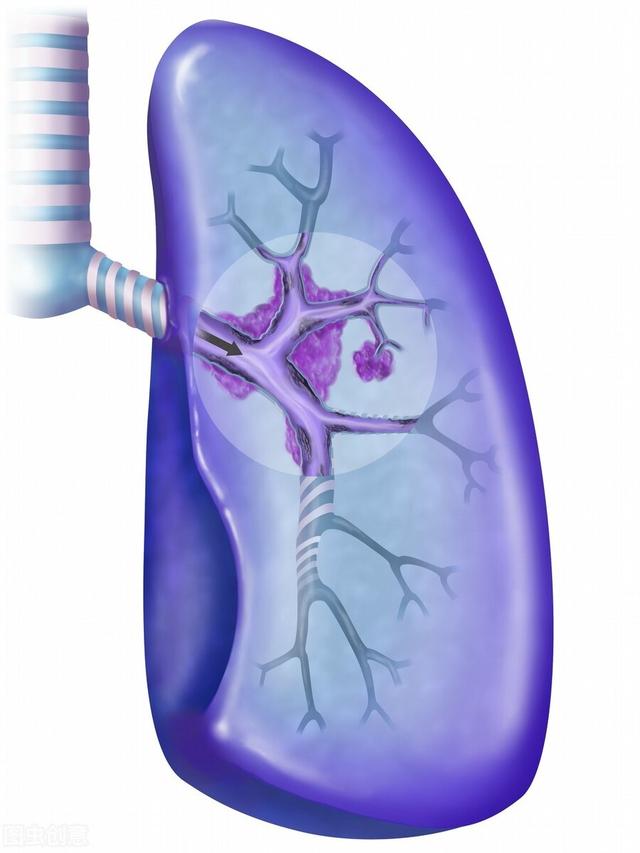

1.呼吸不全は、一般に患者の空気不足として知られ、進行肺癌患者に最も多い。中枢性肺癌では気管や主気管支が閉塞して空気が入りにくくなり、肺の無気肺が大きくなると、次第に息切れや呼吸困難に悩まされるようになる。胸膜転移により大量の胸水が貯留し、肺組織が圧迫されて肺が再開通できなくなる患者もいる。また、肺病変が多すぎて有効呼吸膜面積が著しく減少している患者もいる。これらの理由はすべて、最終的に胸部圧迫感、息切れ、座位呼吸を引き起こし、最終的には呼吸不全に至る。

4.喀血と窒息 肺癌患者の多くは痰に血が混じる症状があり、特に中枢性肺癌の場合、腫瘍が太い血管に浸潤すると喀血が起こり、血液が気道に流れ込んで窒息し、生命が危険にさらされることがある。

人間は、肺の空気交換機能に頼って酸素呼吸を行い、地球上で生存している。肺不全は、巨大な腫瘍、大量の胸水、広範な肺転移、気道閉塞などの進行した肺がんによって引き起こされることが多い。

(1) 呼吸不全で死亡

私たちが呼吸するには両方の肺が必要で、肺が腫瘍でいっぱいになると、呼吸する能力を失い、がんが気道をふさぐこともあり、胸水もたまり、その多量が肺を圧迫して呼吸困難を引き起こす。肺が働けなくなれば、やがて酸素が不足し、全身の臓器が血液と酸素を奪われ、ついには死んでしまう。

(2) 喀血

1.呼吸不全:周知のように、肺は呼吸器の主要な臓器であり、肺がん患者、特に進行期の肺がん患者は、がん細胞が正常な肺組織を破壊するため、呼吸困難に陥ります。がん細胞が脳転移、肝転移、骨転移など全身に広がれば、全身の体内環境が乱れ、呼吸不全の原因にもなる。進行した肺がん患者の大半は、呼吸不全に陥った時点で末期を迎えている可能性があり、家族は心理的な準備をする必要がある。

3.窒息またはショックを引き起こす喀血:腫瘍がガスの通り道を塞ぎ、気管支壁を刺激し、気管が異物を排出しようとするため、咳が生じ、時に痰に血が混じる喀血となる。腫瘍が太い血管に浸潤すると、血管が破裂して喀血することがあり、劇症に血流が流れ込むと窒息やショック状態に陥り、生命を脅かす。一般に、患者が喀血症状を呈した場合は、病気が進行していることを意味する。